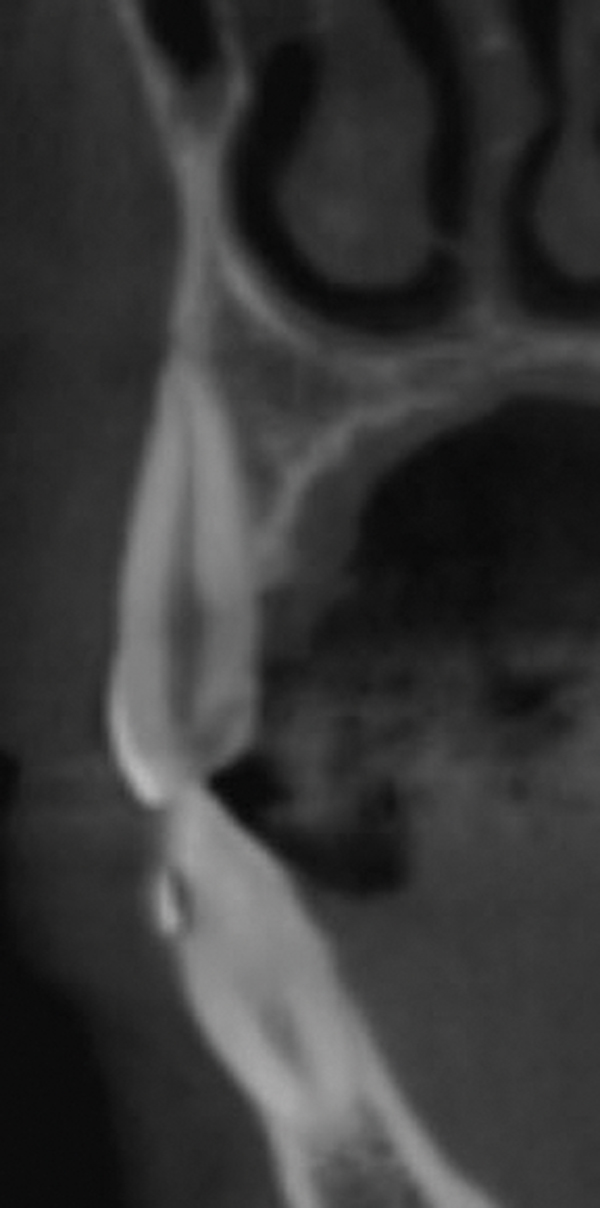

Fig 13 and Fig 14.

Pre- and post-SFOT dentoalveolar

bone presentation. Note the

facial bone augmentation and improved

incisor angle relationship.

Fig 13 and Fig 14. Pre- and post-SFOT dentoalveolar bone presentation. Note the

Figure 14